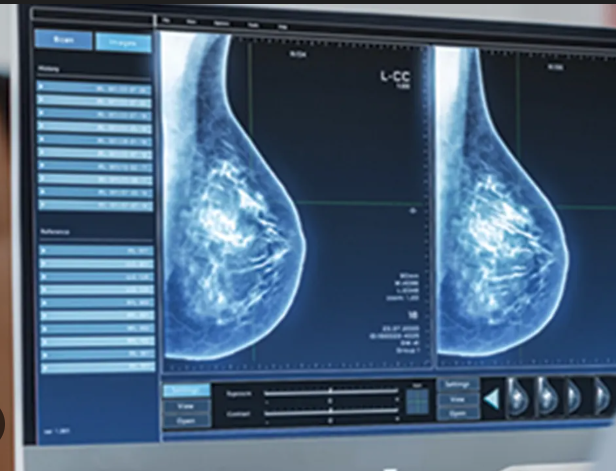

Dijital mamografi, meme dokusunun düşük doz X-ışını kullanılarak görüntülenmesini sağlayan gelişmiş bir radyolojik görüntüleme yöntemidir. Klasik mamografiden farklı olarak, elde edilen görüntüler dijital ortamda işlenir ve büyütülerek daha detaylı incelenebilir.

Bu sayede özellikle çok küçük lezyonlar ve erken evre değişiklikler çok daha hassas bir şekilde tespit edilebilir. Günümüzde meme kanseri taramasında en yaygın kullanılan ve en…